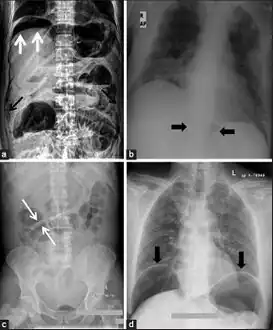

a) X-ray of abdomen, showing subdiaphragmatic free air, air outlining the properitoneal fat stripe black arrows b) Cupola sign arrowheads c) Rigler's sign d) chest radiograph showing free air under the diaphragms

a.b)Pneumoperitoneum developed three days following percutaneous radiologic gastrostomy